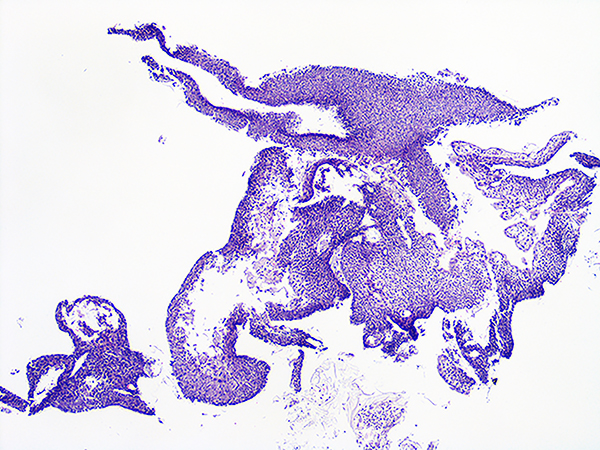

Case 1

Soft Bx CIN 2

10x - Low Power